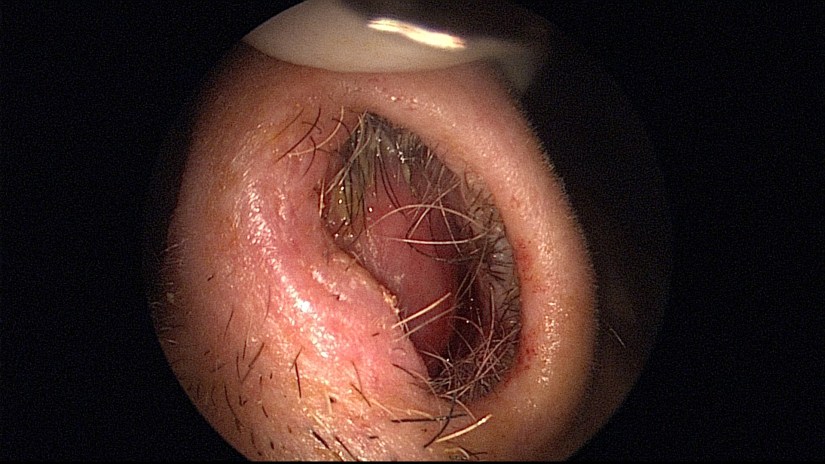

La septoplastie a pour but de corriger une déviation de la cloison nasale.

La déviation de la cloison nasale peut entraîner une obstruction nasale, un ronflement ou favoriser une infection des sinus et parfois des oreilles. Elle peut, dans certains cas, s’associer à une déformation externe du nez.

La septoplastie permet de remodeler la cloison nasale pour améliorer la respiration. Le résultat obtenu sera fonction de l’importance de la déformation anatomique constatée.

L’intervention s’effectue par les voies naturelles, sans cicatrice cutanée, sauf cas exceptionnels où elle pourra nécessiter une incision cutanée minime, peu visible.